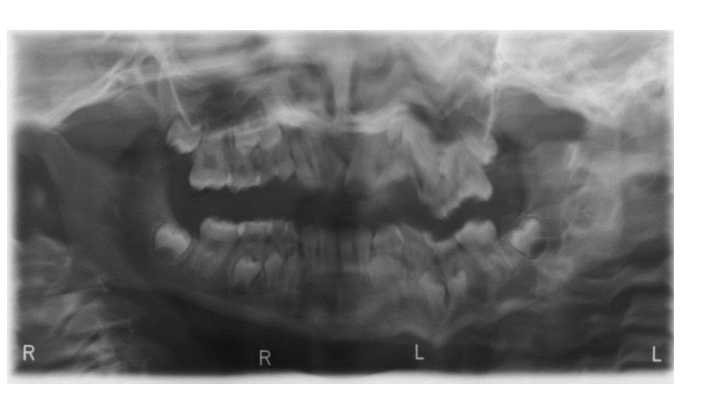

”Rörelse”

Patienten har rört sig under exponeringen vilket ger en vågigt suddig bild som exemplet ovan.